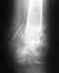

Re: DS: Закрытый оскольчатый перелом шейки и головки левого плеча с удовлетворительным стоянием обломков

На операцию мы пока не решились. И вот почему (моя компиляция мнений нескольких специалистов):

1. Вывиха при переломе нет, плечевой сустав хорошо поддается разработке после сращивания.

2. Операция очень травматична, обязательно образование рубцов на суставе. Пористая часть головки правильной формы не обязательна в будущем, т.к. структура её все равно не восстановится.

3. Оперированный сустав в будущем ведет себя хуже чем не оперированный.

4. Согласно данным Оксфордского медицинского справочника данный тип перелома (без вывиха) 60%-85% корреспондентов рекомендуют лечить консервативно.

5. В случае ошибки при операции последствия слишком тяжелые.

6. Боли артритного характера будут в любом случае.

Так же, есть мнение не менее высокопрофессиональных хирургов-ортопедов о том, что без операции подвижность возможно будет в большой степени ограничена и в будущем преследовать боли.